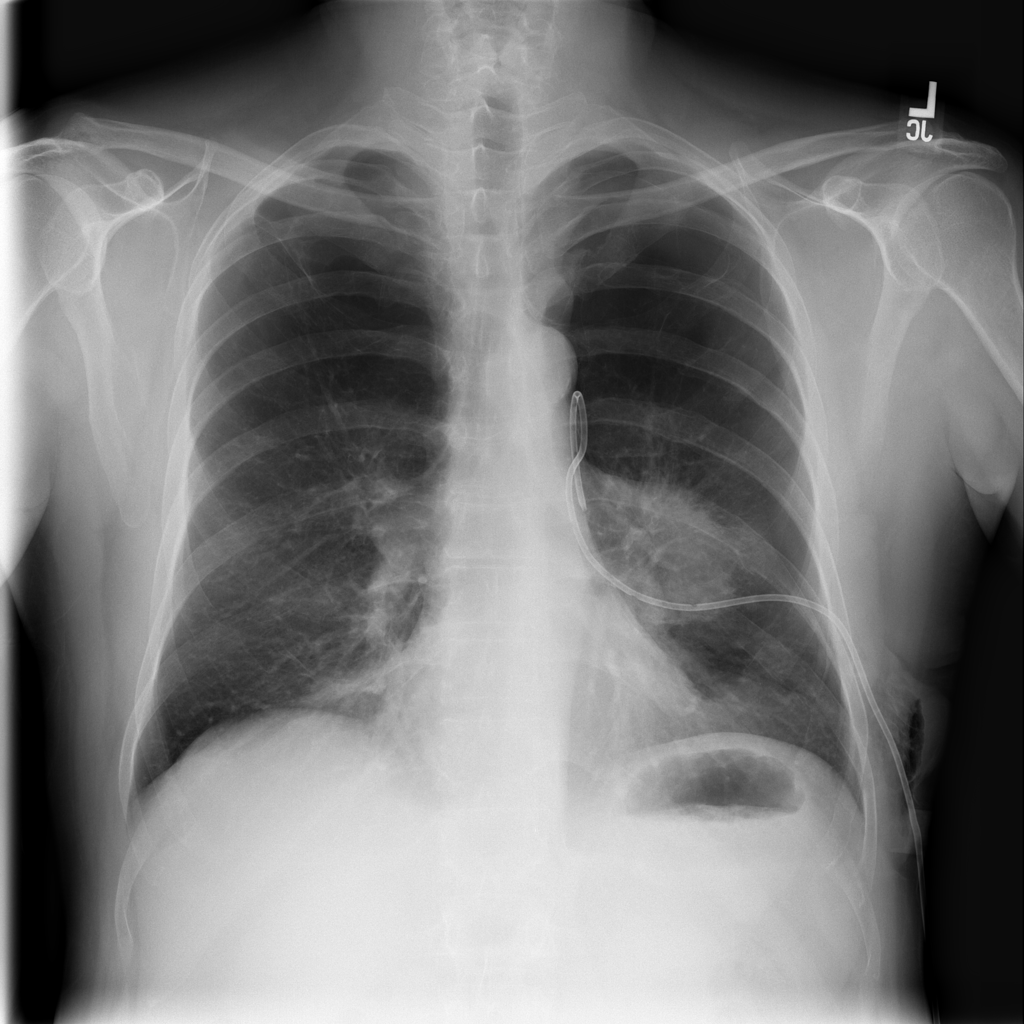

PAT-4639 · IMG-012Pneumothorax

PAT-4639 · IMG-012

AP